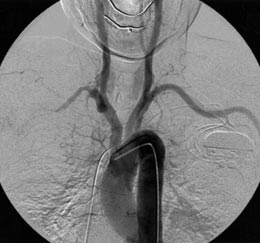

| Fig.

3b |

Arch arteriography; other arteries

showed normal finding |